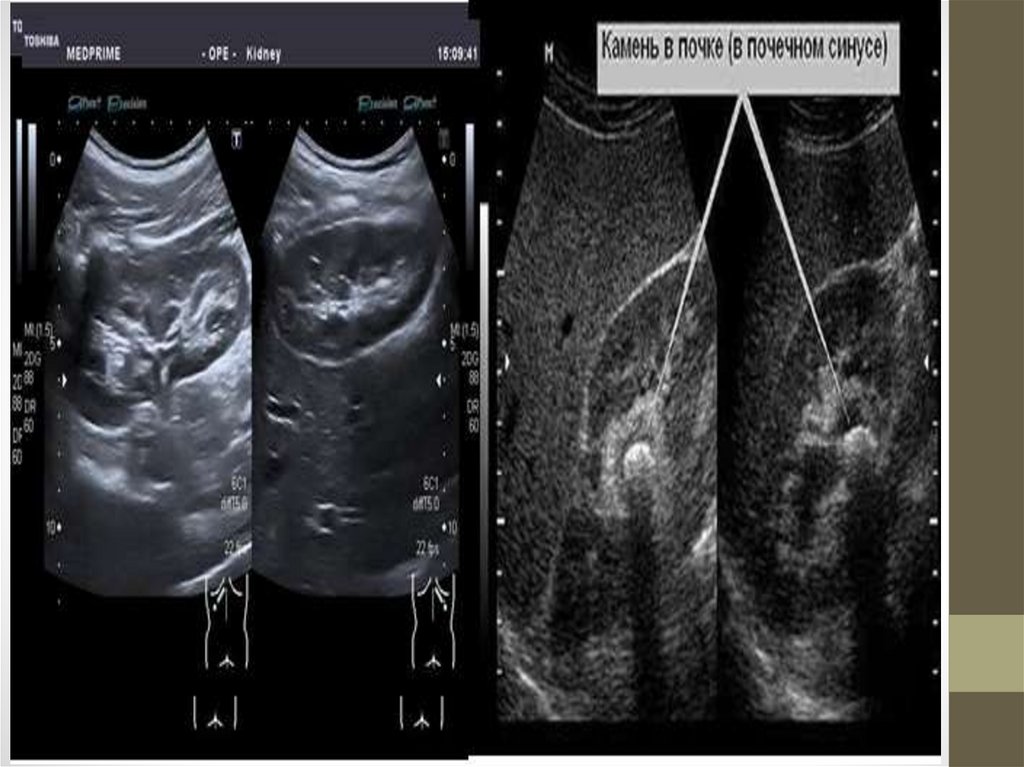

• Инструментальные: УЗИ, сканирование. КТ, МРТ,

ангиография почечных артерий.

• Специальные исследования: УЗИ, радионуклидная ренография,

сканирование, динамическая сцинтиграфия.

• При обследовании: (рентгенологическое, УЗИ)

выявляются камни, особенно хорошо выявляются

ураты, хуже - фосфаты.

• Рентгенологическое исследование, компьютерная

томография, радиоизотопное сканирование выявляют

тени конкрементов в почках.